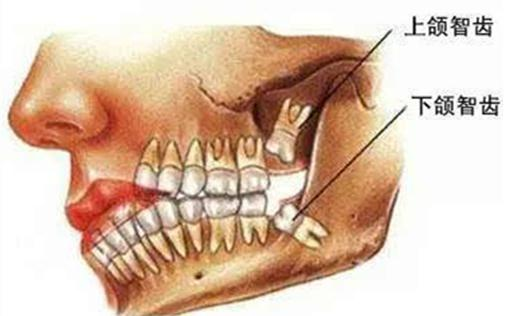

什么是智齿?

智齿是指人类口腔内牙槽骨上最里面的第三颗磨牙,从正中的门牙往里数刚好是第八颗牙齿。由于它萌出时间很晚,一般在16~25岁间萌出,此时人的生理、心理发育都接近成熟,有“智慧到来”的象征,因此被俗称为“智齿”。